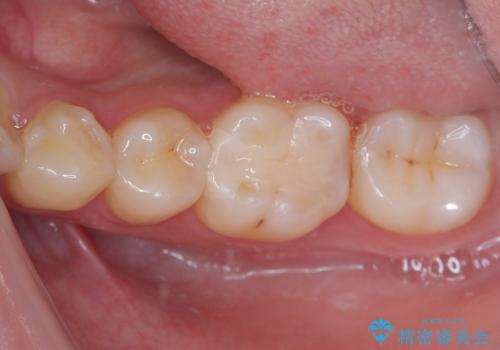

精度の良いインレーを製作するために、シリコーンにて型どりしました。

また確実な接着操作を行うために、インレーを接着する際にはラバーダム防湿を行いました。

銀歯を気にせずに笑うことができると満足していただきました。